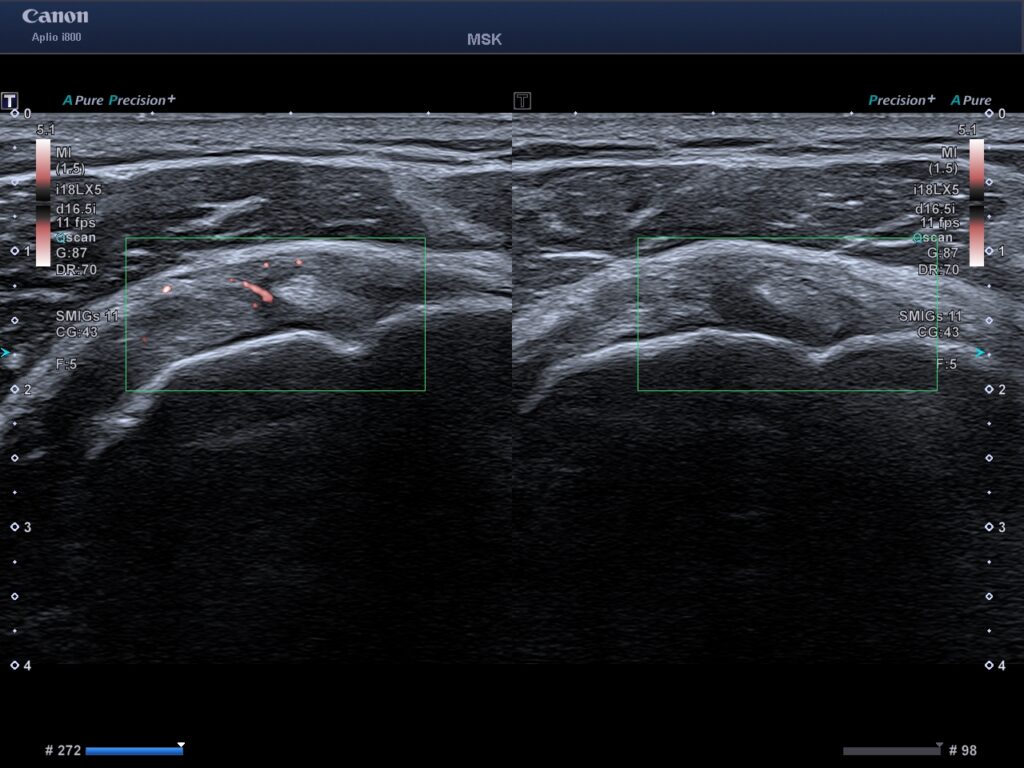

Till vänster ses ledkapseln förtjockad vid ultraljudsundersökning. Till höger ses den symtomfria axel.